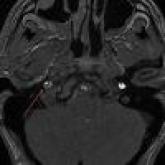

Internal Carotid Artery Dissection After Indirect Blunt Cervical Trauma in an Ice Hockey Goaltender

Internal carotid artery dissections are rare injuries that can result from both direct cervical trauma and indirect trauma causing sudden cervical...